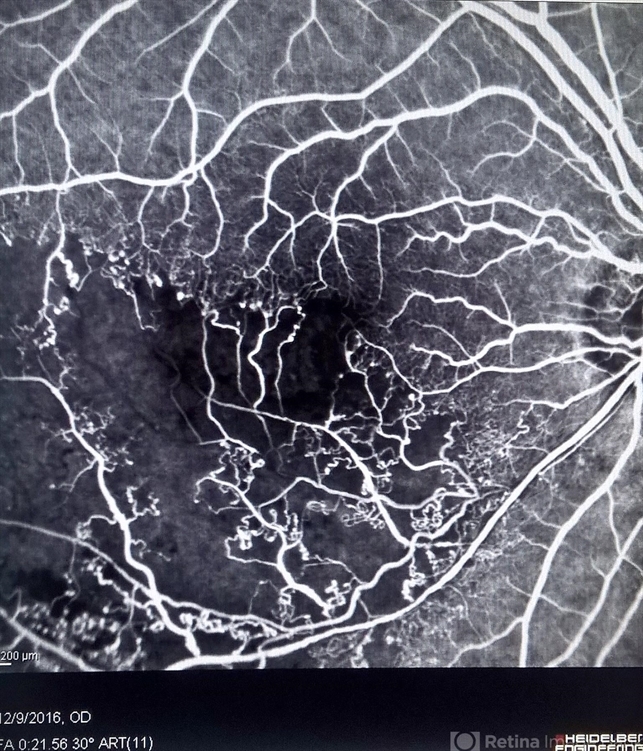

- oclus, occlusion of partial of retinal vein, occlusion of retinal vein

- JEFFERSON R SOUSA - Study Center and Ophthalmological Research Dr. Andre M V Gomes, Institute Dr. Suel Abujamra São Paulo-Brazil

Heidelberg Engineering HRA - 2 or Spectralis Angiograph, 30 degrees. - Description

- Male patient, 55 years old, with low vision in the right eye. In the retinal mapping examination and color photography, important alterations were observed suggesting an occlusion of the inferior vein. It was later confirmed in fluorescein angiography.